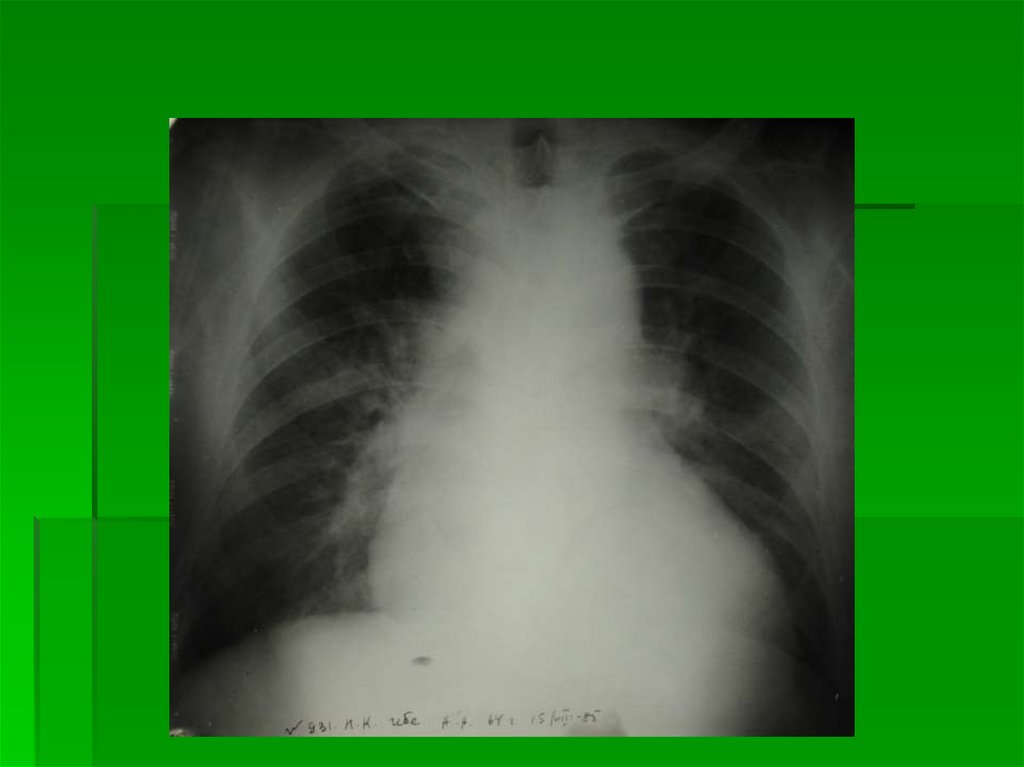

13.

1 степень

Перераспределение

кровотока в МКК

14.

15.